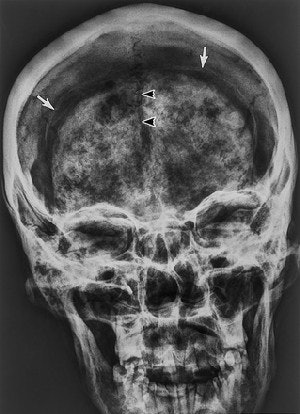

![]() |

| This radiograph, taken in May 1993, shows variable shrinkage of the brain. The body was in a supine position. The frontal view of the head shows the shrunken brain surrounded by dura mater (arrows) that did not shrink as much as the brain did. The arrowheads point out the falx cerebri within the interhemispheric fissure. The brain exhibits variable opacity, probably due to variation in the physical and chemical alterations that accompanied an intermittent or inhomogeneous mummification process. Murphy WA Jr., zur Nedden D, Gostner P, Knapp P, Recheis W, Seidler H. "The Iceman: discovery and imaging," (Radiology 2003, Vol. 226, pp. 614-629). |